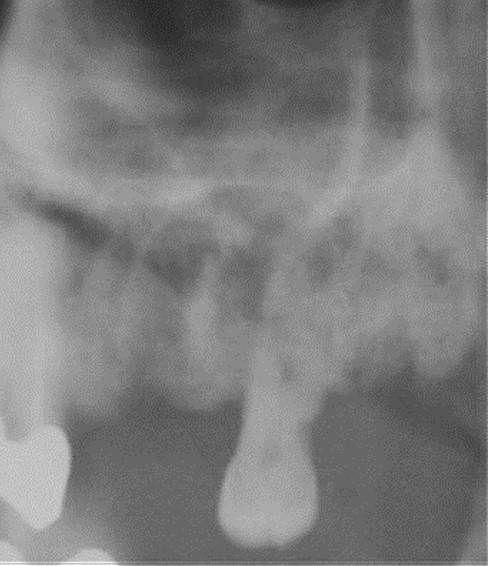

Radiologica:

OPT

Segni precoci:

- Ispessimento cresta alveolare e lamina dura

- Persistenza alveolo post-estrattivo

- Sequestro

- Allargamento spazio parodontale

Segni tardivi:

- Frattura patologica

- Ispessimento canale osseo Nervo Alveolare Inferiore

- Osteosclerosi diffusa

- Radiopacità seno mascellare

- Reazione periostale

caso di osteonecrosi mandibolare inferiore di destra